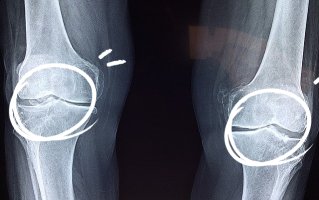

콘드로이틴은 연골에서 발견되는 가장 두드러진 물질입니다. 그것은 무릎의 골관절염 환자에게 도움이 될 수 있는 분해로부터 세포를 보호하고 유지함으로써 기능합니다. 여러 연구에 따르면 연골 손실률도 개선할 수 있습니다.